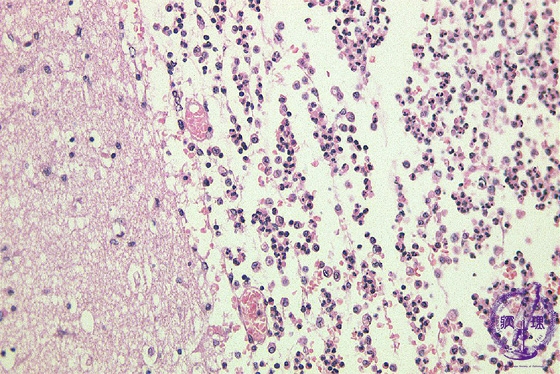

Microscopic findings (H.E. high magnification): Infiltrating inflammatory cells were mainly neutrophils and macrophages.